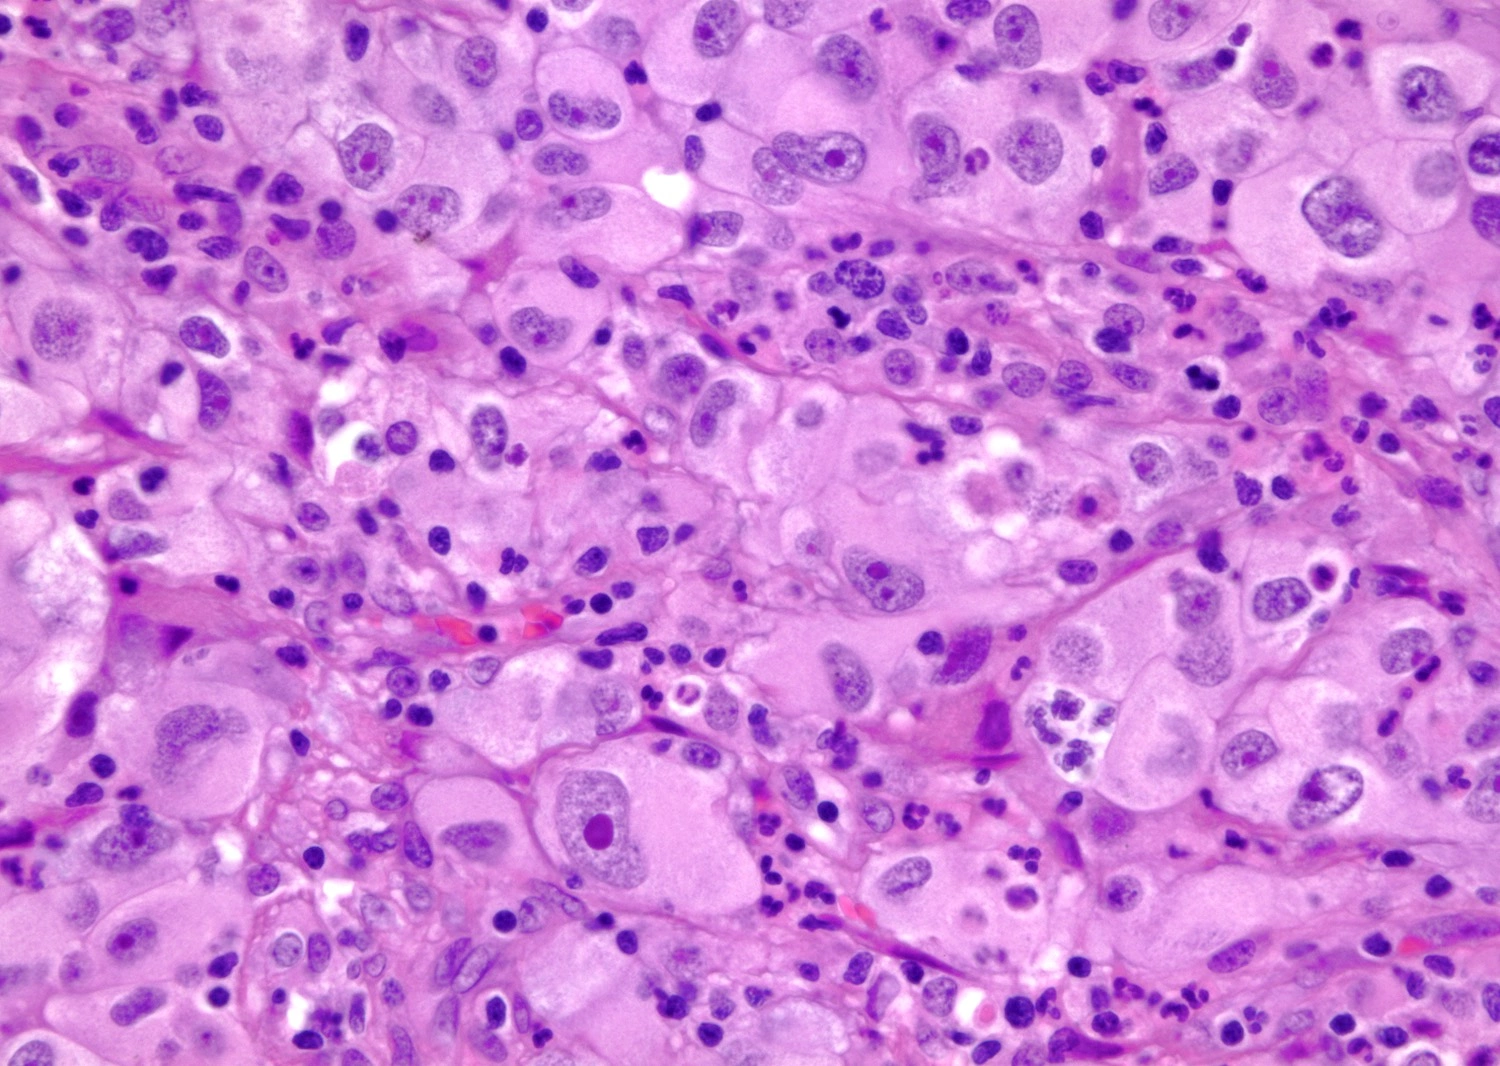

Наиболее распространённым является почечно-клеточная карцинома — 85% случаев заболевания. Она развивается в проксимальных почечных канальцах, отвечающих за фильтрацию крови.

Гистология почечно-клеточного рака (увеличение 400х)

Уротелиальная карцинома, также известная как переходно-клеточная карцинома, составляет 5-10% случаев у взрослых. Этот тип рака начинается в области почечной лоханки.